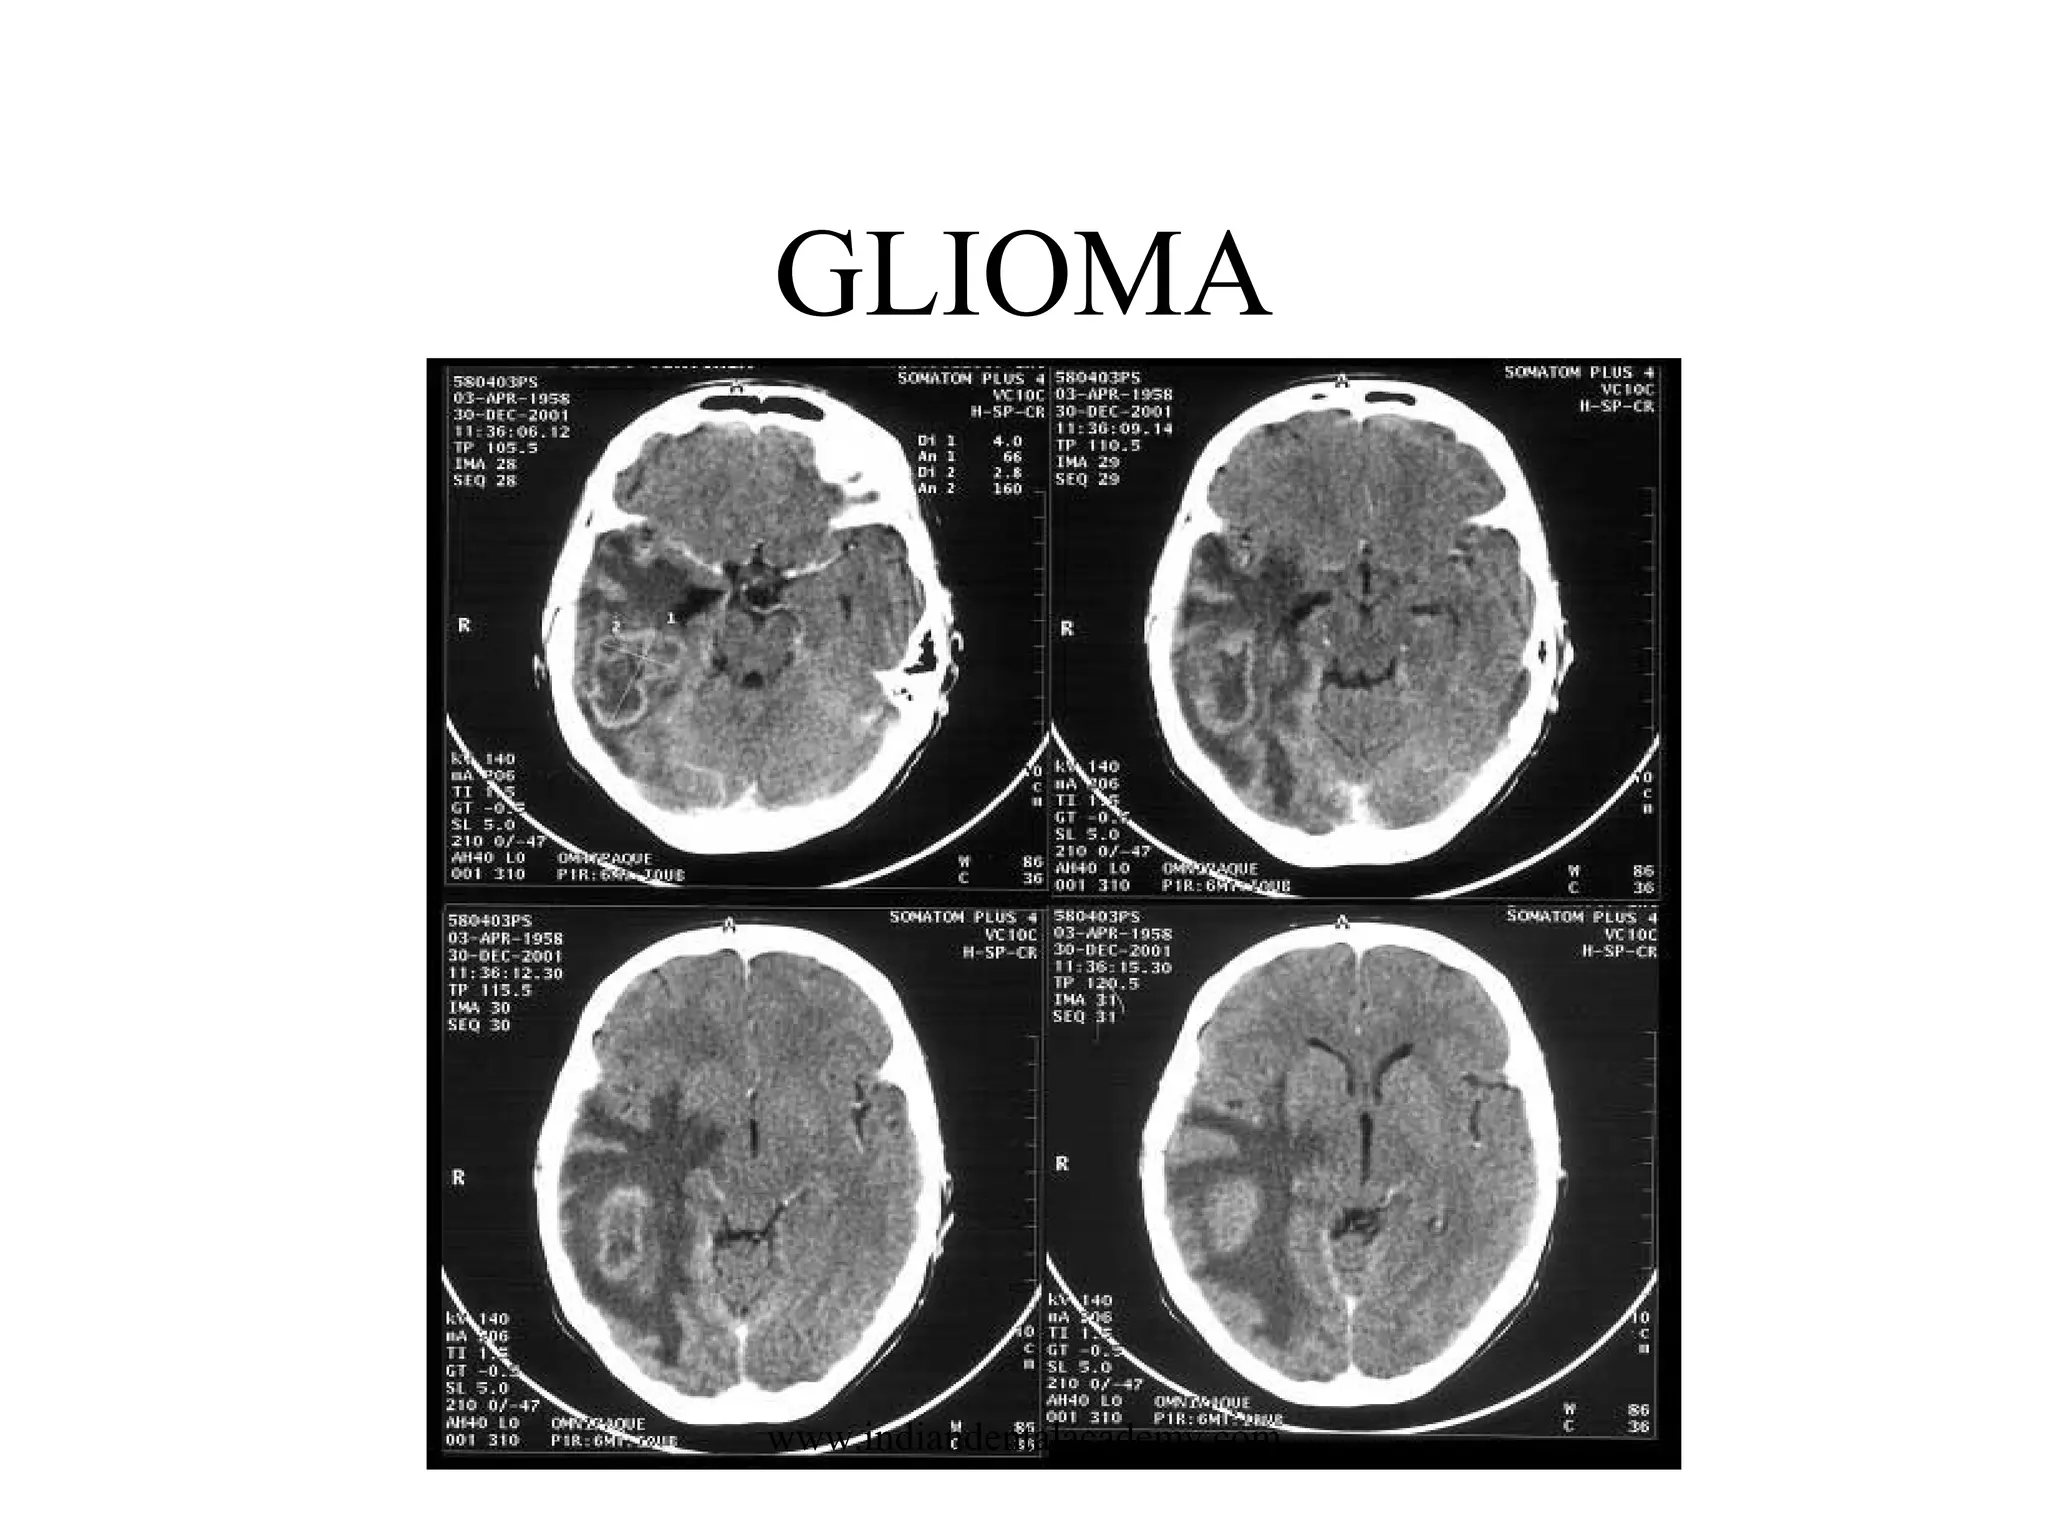

•Brain stem gliomas

are tumors found in the brain stem. Most brain stem tumors

cannot be surgically removed because of the remote location and

delicate and complex function this area controls. Brain stem

gliomas occur almost exclusively in children; the group most

often affected is the school-age child. The child usually does not

have increased intracranial pressure, but may have problems with

double vision, movement of the face or one side of the body, or

difficulty with walking and coordination

GLIOMA

www.indiandentalacademy.com